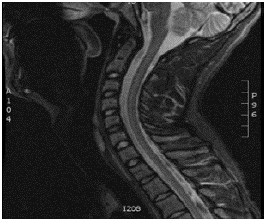

That same day, the patient was admitted to the Clinica Universitaria Colombia in Bogotá D.C. due to suspicion of transverse myelitis based on a feeling of stabbing pain in the thoracic spine, associated with hemiparesis of the left side of the body with predominance in the upper limb, mild respiratory difficulty, hyporeflexia and non-voluntary loss of 2kg of weight in 1 week. A cervical spine MRI was performed, showing an alteration in spinal cord signal intensity in the cervical segment, correlated with the affected cervical sensory level. This finding allowed diagnosing longitudinally extensive transverse myelitis (LETM) (Figures 1 and 2), so the patient was admitted to the hospital to start therapy with methylprednisolone pulses at a dose of 1g intravenously every 24 hours for 5 days. In addition, immunophenotyping and diagnostic studies were performed, obtaining negative LETM.

Contrast nuclear magnetic resonance of the cervical spine (sagittal plane) that shows chronic changes in signal intensity and malacia in the anterior cords from level C2 to level C4.

Figure 2: Contrast nuclear magnetic resonance of the cervical spine (sagittal plane) that shows chronic changes in signal intensity and malacia in the anterior cords from level C2 to level C4.

Source: Document obtained during the study.